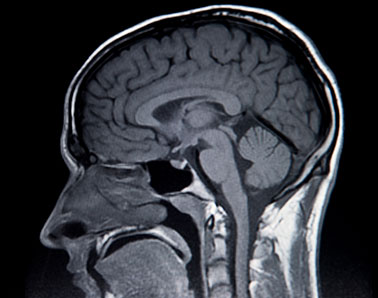

Lima Memorial Health System provides neurology and neurosurgery services for patients in Lima and surrounding northwest Ohio communities. Our neurology team diagnoses and treats disorders of the brain, spinal cord and nervous system using non-surgical care. When surgery is needed, our neurosurgery team treats conditions affecting the brain, spine and peripheral nerves.

Our neurology team diagnoses and manages disorders affecting the central and peripheral nervous systems. We evaluate conditions affecting the brain, spinal cord and nerves and develop treatment plans tailored to each patient’s symptoms and needs.

Lima Memorial’s neurosurgery team provides surgical treatment for disorders affecting the central and peripheral nervous system. We treat conditions involving the brain, spine and peripheral nerves with a focus on patient safety and coordinated care.